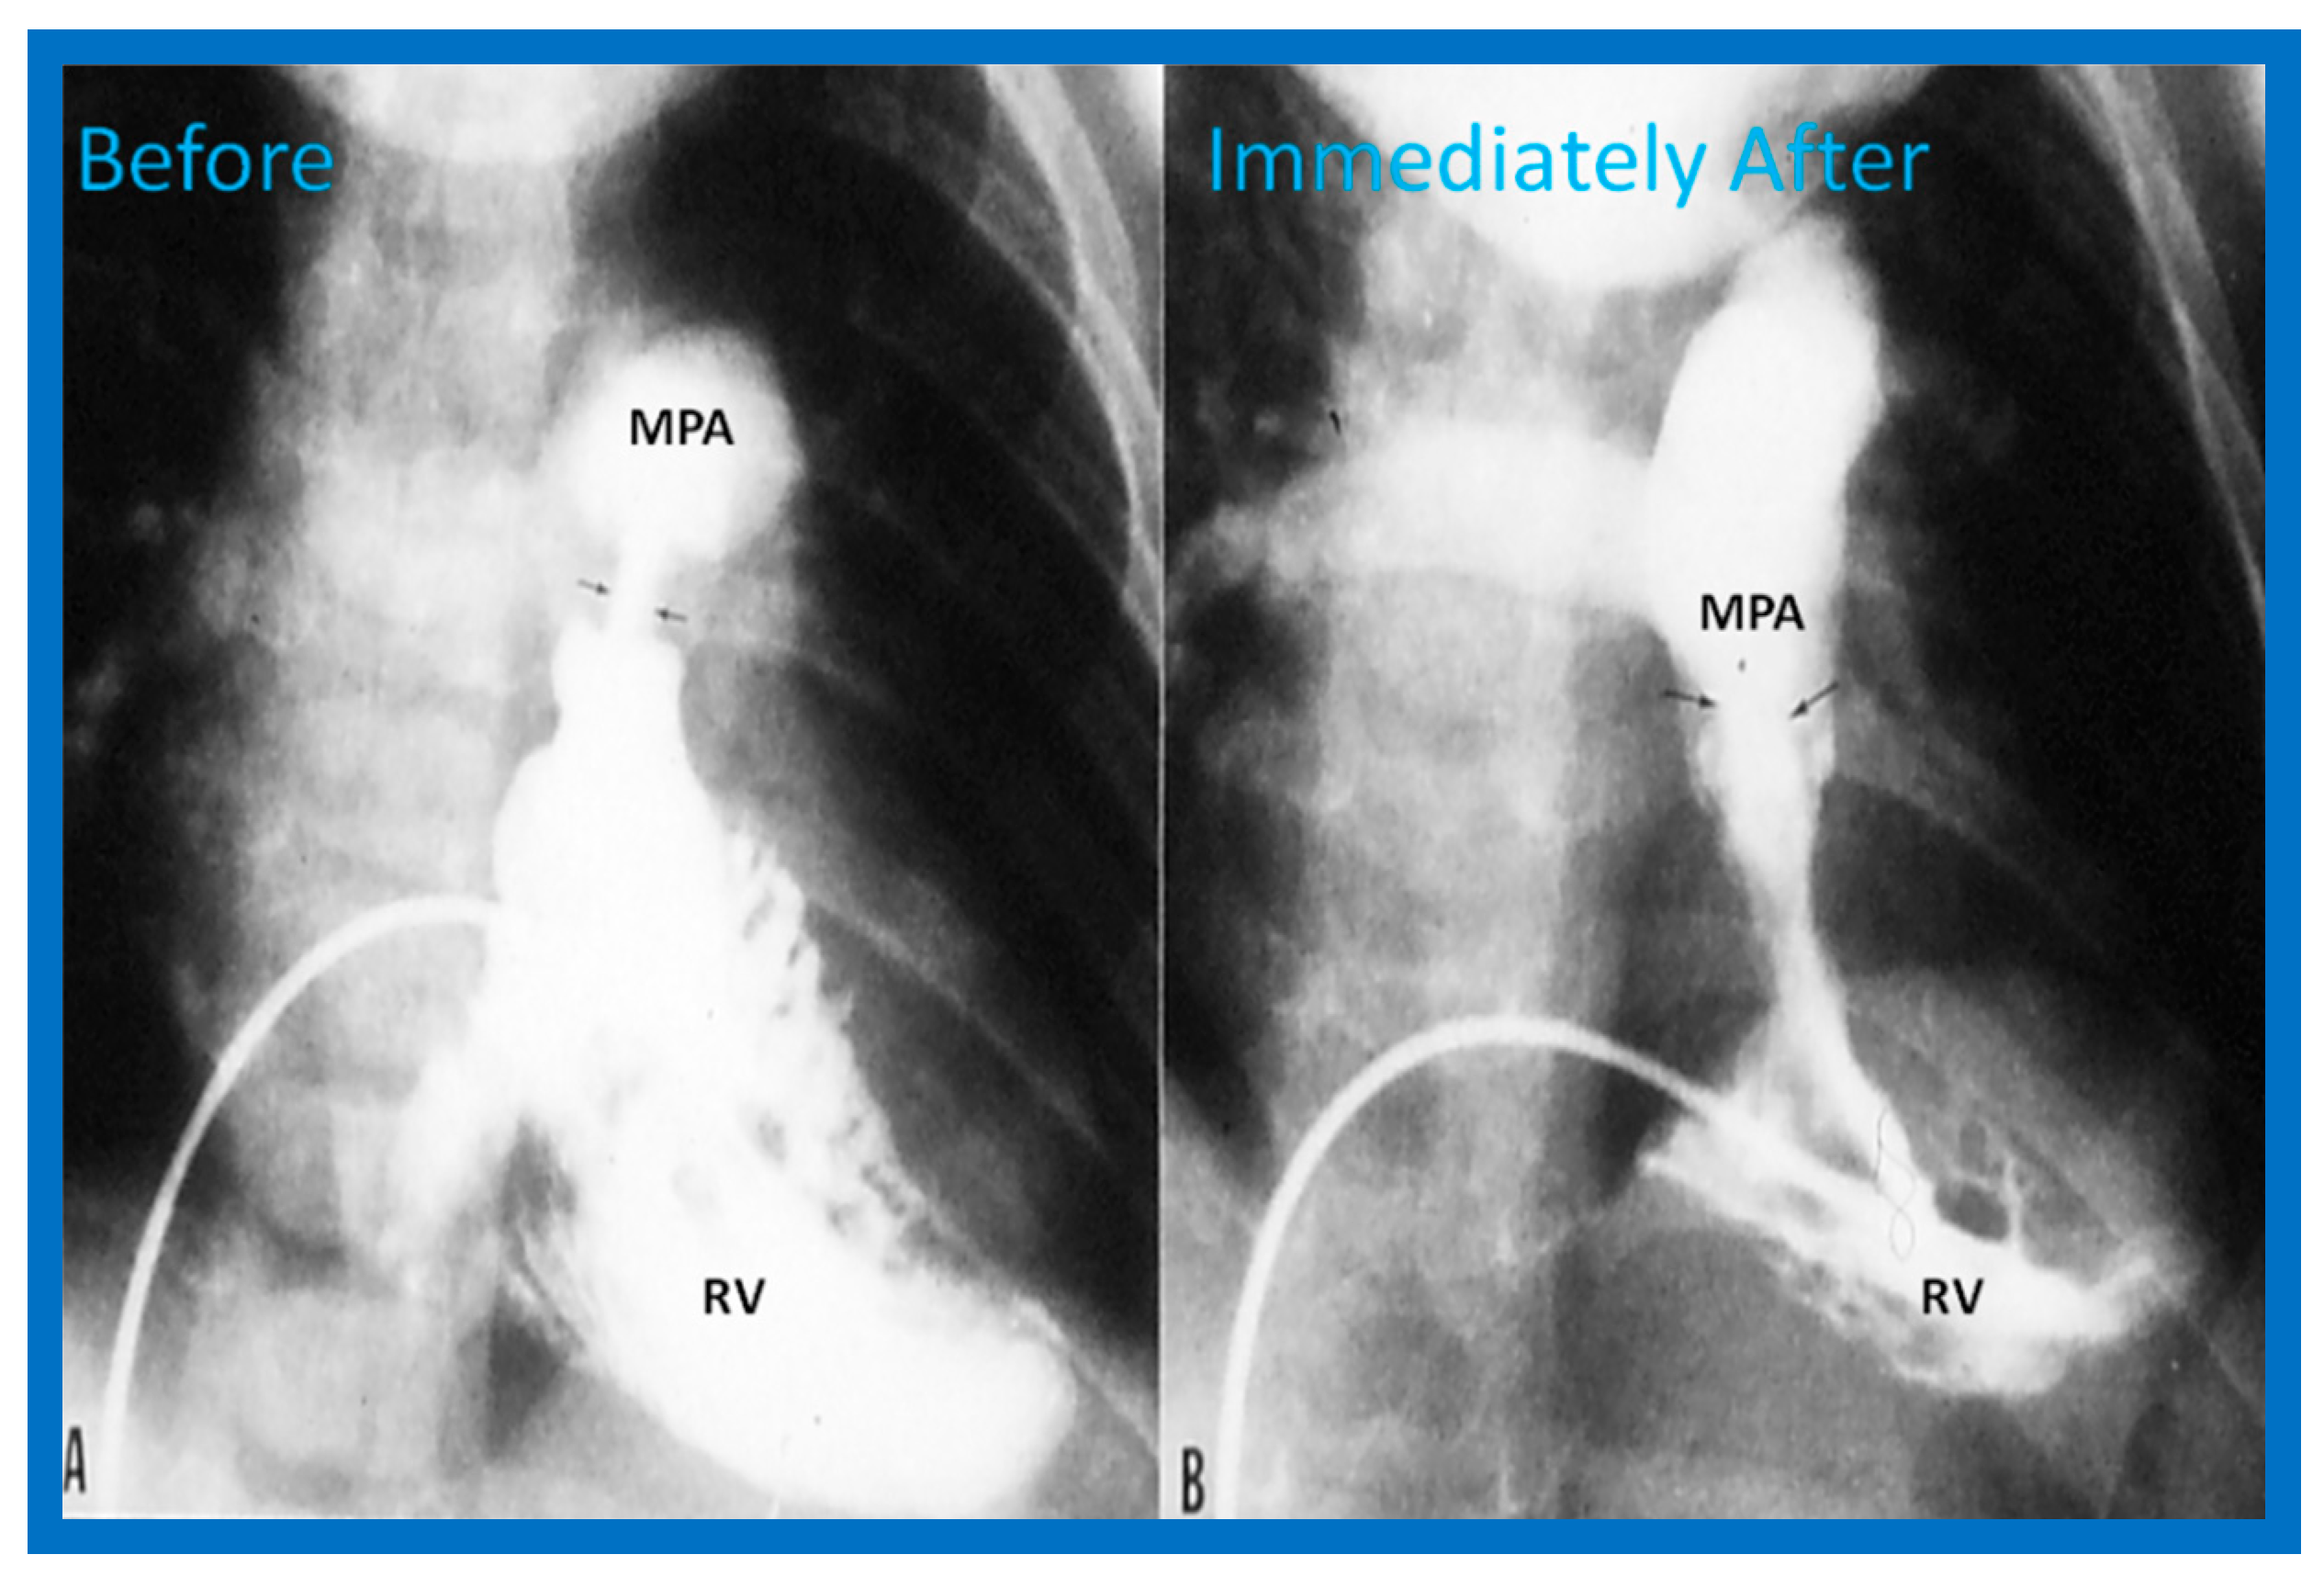

- Thapar, M.K.; Rao, P.S. Significance of infundibular obstruction following balloon valvuloplasty for valvar pulmonic stenosis. Am. Heart J. 1989, 118, 99–103. [Google Scholar] [CrossRef] [PubMed]